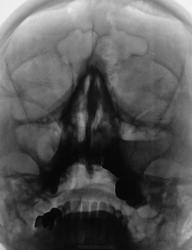

Снижение пневматизазии в проекции ячеек решетчатой кости, горизонтальный уровень в левой в/челюстной пазухе до 2/3 объёма.

пневматизация левой верхне челюстной пазухи снижена за счет пристеночного отека слизистой и выпота...

остальные пазухи воздушные...